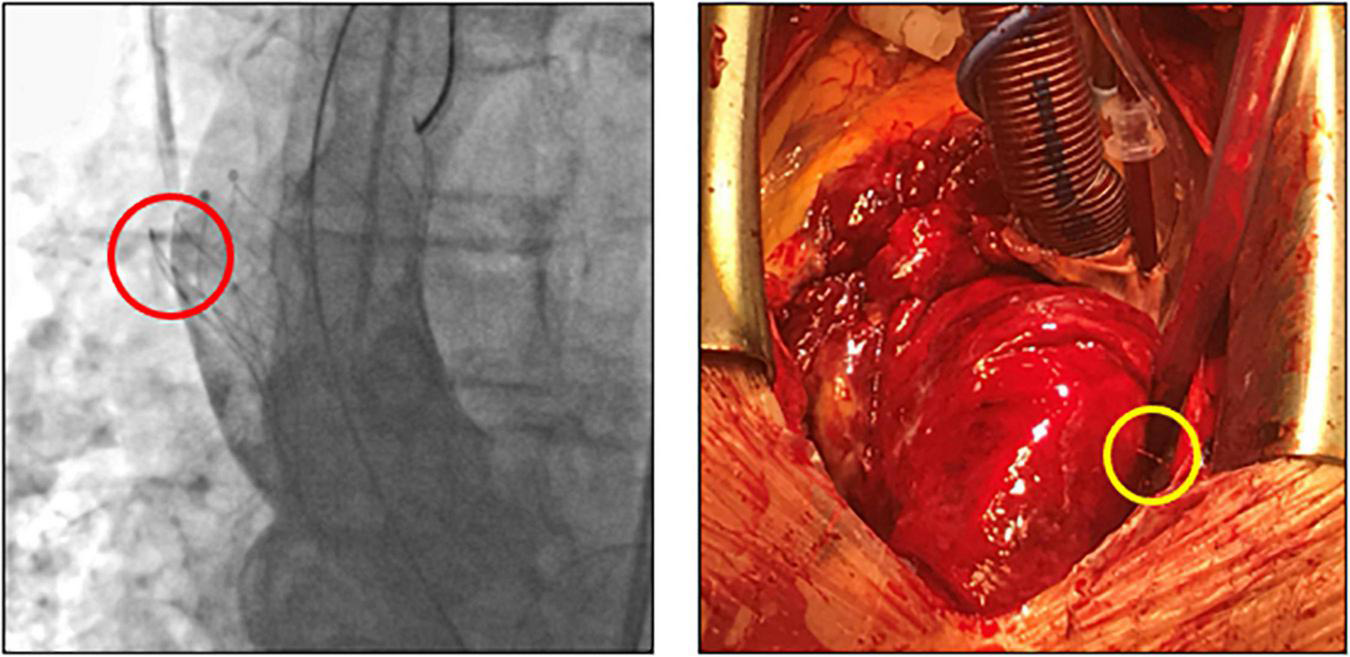

Subclinical leaflet thrombosis characterized by hypoattenuated leaflet thickening (HALT) is a frequent finding in transcatheter bioprosthetic aortic valves with a prevalence of up to 28% in short- and long-term CT follow-up (4, 5, 14). To our knowledge, our study is the first to systematically examine embolized valves by CT after mid- to long-term follow-up. HALT was detected in the embolized valves in two TVEM patients (Figure 2). Since the number of patients in our imaging sub-study is low it is not possible to draw definite conclusions. Of note, both patients with HALT did not take oral anticoagulants which have been shown to prevent the formation of leaflet thrombosis. In addition, our findings advise some caution as parts of the upper crown of embolized self-expanding valves protruding into the aortic wall were observed in three patients (Figure 3). This is reminiscent of another case from our TVEM cohort complicated by valve embolization due to pop-up of a 25 mm Portico self-expanding valve. The embolized valve was snared and pulled into the ascending aorta to avoid coronary obstruction. After successful implantation of a second transcatheter valve (23 mm Edwards Sapien 3) the patient developed hemorrhagic shock. Angiography revealed perforation of the ascending aorta by a part of the upper crown of the THV protruding through the aortic wall. The valve was surgically removed, and the ascending aorta repaired on cardiopulmonary bypass (Figure 6). Accordingly, interventionalists should be aware of this potential complication when embolized valves have to be actively pulled up into the ascending aorta using a snare. Patients should be examined by CT in a timely fashion to rule out perforation of the ascending aorta if they develop hemodynamic instability in the postinterventional course.

FIGURE 6

Fluoroscopic images and intraoperative situs after perforation of the ascending aorta by an embolized self-expanding valve. Fluoroscopy (left) and intraoperative situs (right) of a patient with hemorrhagic shock due to perforation (circles) of the ascending aorta. After embolization, the self-expanding valve (25 mm Portico) was deliberately pulled further into the ascending aorta to avoid coronary obstruction.